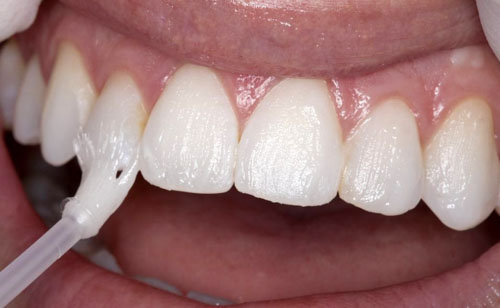

2. Trám răng thẩm mỹ

Dùng vật liệu chuyên dụng để che phủ vùng men bị mòn và bảo vệ răng khỏi vi khuẩn.